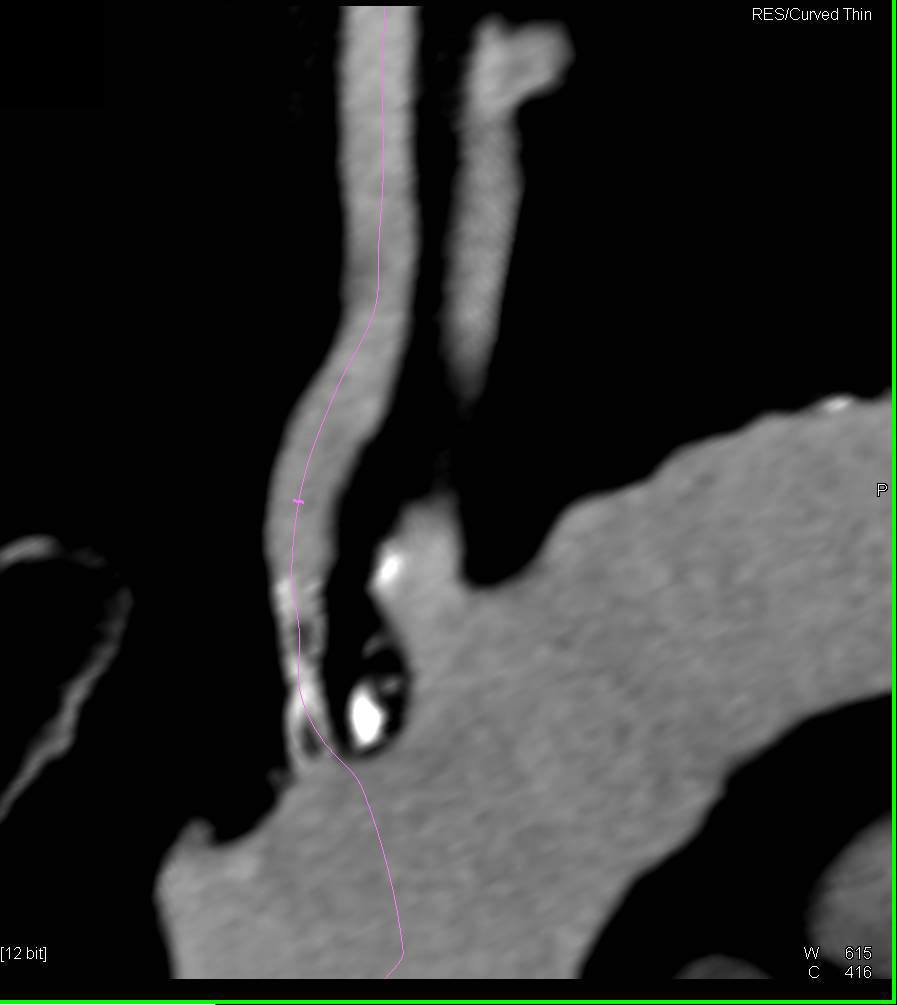

Aortic Dissection with Early and Late Phase Images